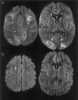

Chronic punctate sialadenitis

Parotitis is an inflammation of one or both parotid glands, the major salivary glands located on either side of the face, in humans. The parotid gland is the salivary gland most commonly affected by inflammation. [Source: Wikipedia ]